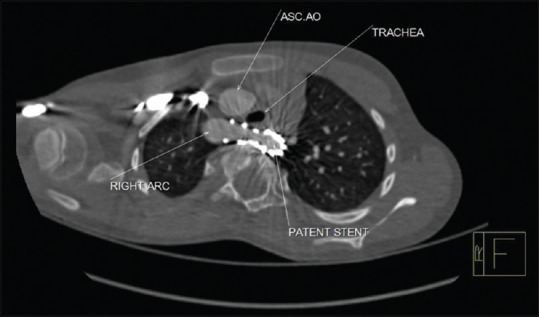

The left subclavian artery (LSCA) was hypoplastic and filled late in the initial aortography [Video 13], indicative of an isolated LSCA. LSCA was not in the vicinity of the coarctation stenting. Fortunately, despite having the substrate for a vascular ring as previously reported, the patient developed no respiratory symptom or difficulty in eating solid foods after the stenting [Figure 2].

Figure 2.

Width (Px): 1280, Height (Px): 834. Color Depth: This computed tomographic image shows patency of the trachea after at the trachea at the end of the stenting procedure